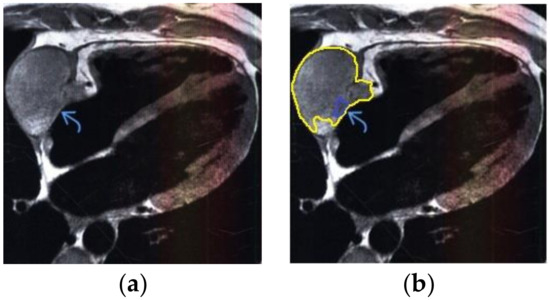

The contour extraction method was used to identify cancerous areas that, after applying the model to eliminate mixed noise, had an increased contrast of volumetric heterogeneous formations in the region of the heart [27]. This method was developed by the authors when analyzing thermal images to assess the condition of the coronary vessels of the myocardium under cardiopulmonary bypass. The contours of the cancerous regions in the examples used for applying the model to eliminate mixed noise (Figure 4, Figure 5, Figure 6, Figure 7, Figure 8 and Figure 9) are highlighted in yellow and they represent the visual boundary of the distribution of volumetric heterogeneous formations.

• For a patient with a history of melanoma: during MRI with contrast enhancement, a volumetric formation adjacent to the atrial septum was visualized in the left atrium (Figure 5).

Figure 5. Heart MRI: (a) image with white noise and (b) denoised image with contrast enhancement of volume melanoma in the left atrium.